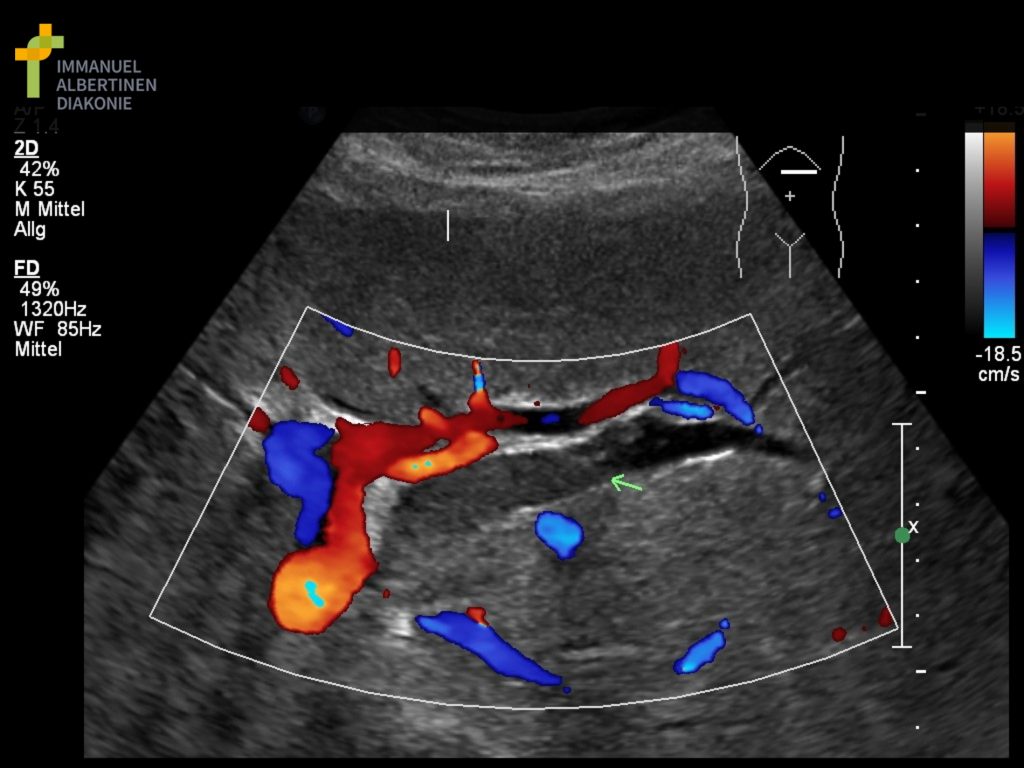

Der Ultraschall (die Sonographie) ist ein etabliertes, nicht-invasives Bildgebungsverfahren zur Beurteilung innerer Organe. Er ist schmerzfrei, ohne Strahlenbelastung und eignet sich sowohl zur Abklärung von Beschwerden als auch zur Verlaufs- und Vorsorgeuntersuchung.

Bauch-Ultraschall (Abdomen-Sonographie)

Der Ultraschall des Bauchraums dient der Untersuchung von Leber, Gallenblase, Bauchspeicheldrüse, Milz, Nieren und ableitenden Harnwegen. Er wird häufig eingesetzt bei:

Die Abdomensonographie liefert rasch verwertbare Befunde und ist ein zentrales Instrument der internistischen Basisdiagnostik.